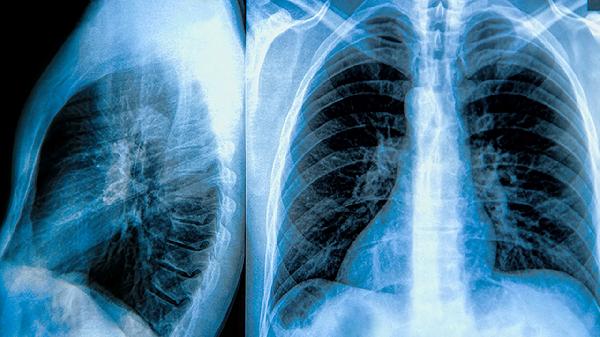

3、诊断肺大泡主要依靠影像学检查,如胸部X线或CT。胸部X线可初步发现肺大泡,但CT能更清晰地显示其大小、位置及周围肺组织情况,有助于评估病情严重程度。